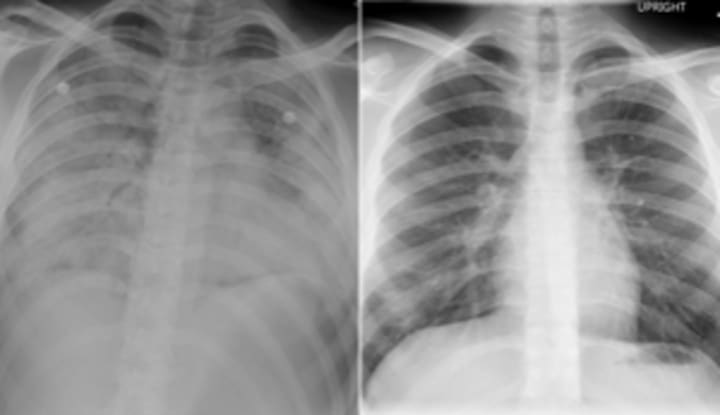

VAPI. Vape Associated Pulmonary (Lung) Illness. While studies have been suggesting a link for years, we now know for a fact that a common fungicide, Myclonozole (used in cultivation to treat mold) combines with butane (a solvent commonly used in oil extraction) to create myclobutanil, which when heated above 247 degrees F, degrades and releases Hydrogen Cyanide. Defined by a Google Search: Hydrogen cyanide (AC) is a chemical warfare agent (military designation, AC). It is used commercially for fumigation, electroplating, mining, chemical synthesis, and the production of synthetic fibers, plastics, dyes, and pesticides.

Aerosolizers, or thinners, are added to the waxy THC oil extract to make it more runny, about the consistency of Honey; hence the name BHO – Butane Honey Oil. Runnier consistency helps the vape pen do a better job turning liquid into a gas for inhalation. Coconut Oil, Poly Ethylene Glycol (PEG) and Vitamin E Acetate are the most prevalent ‘cut’ used by THC Cartridge makers because they are cheap and ‘available’. ‘Available’ for use in cosmetics as key ingredients in skin moisturizers. Moisturizers create a boundary to trap moisture in the skin instead of allowing it to evaporate. All three of these chemicals are currently banned for ingestion in the European Union, but not in the United States. Ingestion occurs when used as an inhalant. These compounds do the same thing inside your lungs; they create a boundary layer. Unfortunately, the boundary created is between lung tissue and air, inhibiting oxygen from being delivered to your body in the short run and causing acute lung tissue necrosis over time.